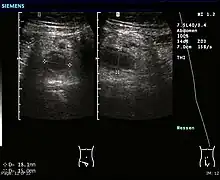

Ultrasound

Abdominal ultrasonography, preferably with doppler sonography, is useful to detect appendicitis, especially in children. Ultrasound can show the free fluid collection in the right iliac fossa, along with a visible appendix with increased blood flow when using color Doppler, and noncompressibility of the appendix, as it is essentially walled-off abscess. Other secondary sonographic signs of acute appendicitis include the presence of echogenic mesenteric fat surrounding the appendix and the acoustic shadowing of an appendicolith.[57] In some cases (approximately 5%),[58] ultrasonography of the iliac fossa does not reveal any abnormalities despite the presence of appendicitis. This false-negative finding is especially true of early appendicitis before the appendix has become significantly distended. Also, false-negative findings are more common in adults where larger amounts of fat and bowel gas make visualizing the appendix technically difficult. Despite these limitations, sonographic imaging with experienced hands can often distinguish between appendicitis and other diseases with similar symptoms. Some of these conditions include inflammation of lymph nodes near the appendix or pain originating from other pelvic organs such as the ovaries or Fallopian tubes. Ultrasounds may be either done by the radiology department or by the emergency physician.[59]